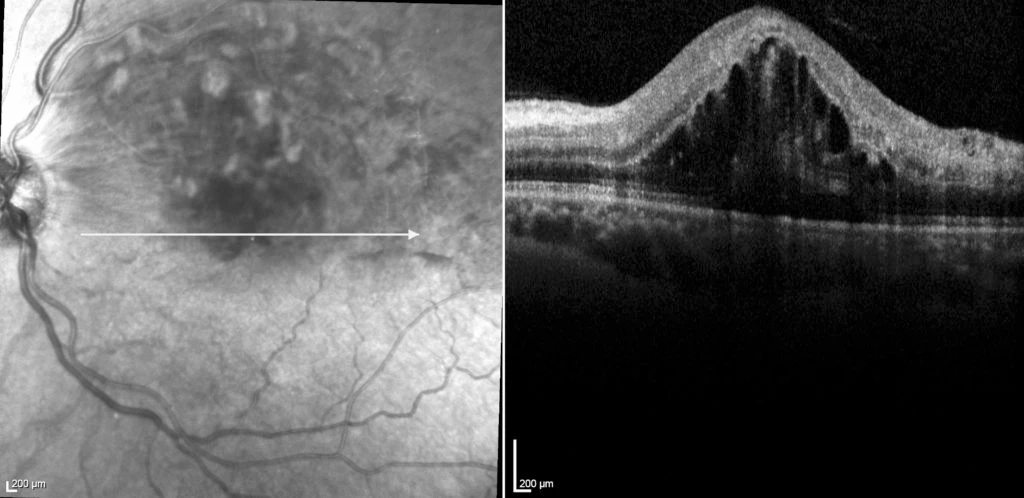

On examination his corrected acuities were right 6/6 and left 6/90. His intraocular pressures were normal. His anterior segments were unremarkable with clear ocular media and no rubeosis. Dilated fundus examination on the right was essentially unremarkable and on the left there were retinal haemorrhages and cotton-wool spots, along the superotemporal arcade, consistent with a branch retinal vein occlusion. On OCT scanning, he had significant associated macular oedema (see figure 1).

Figure 1